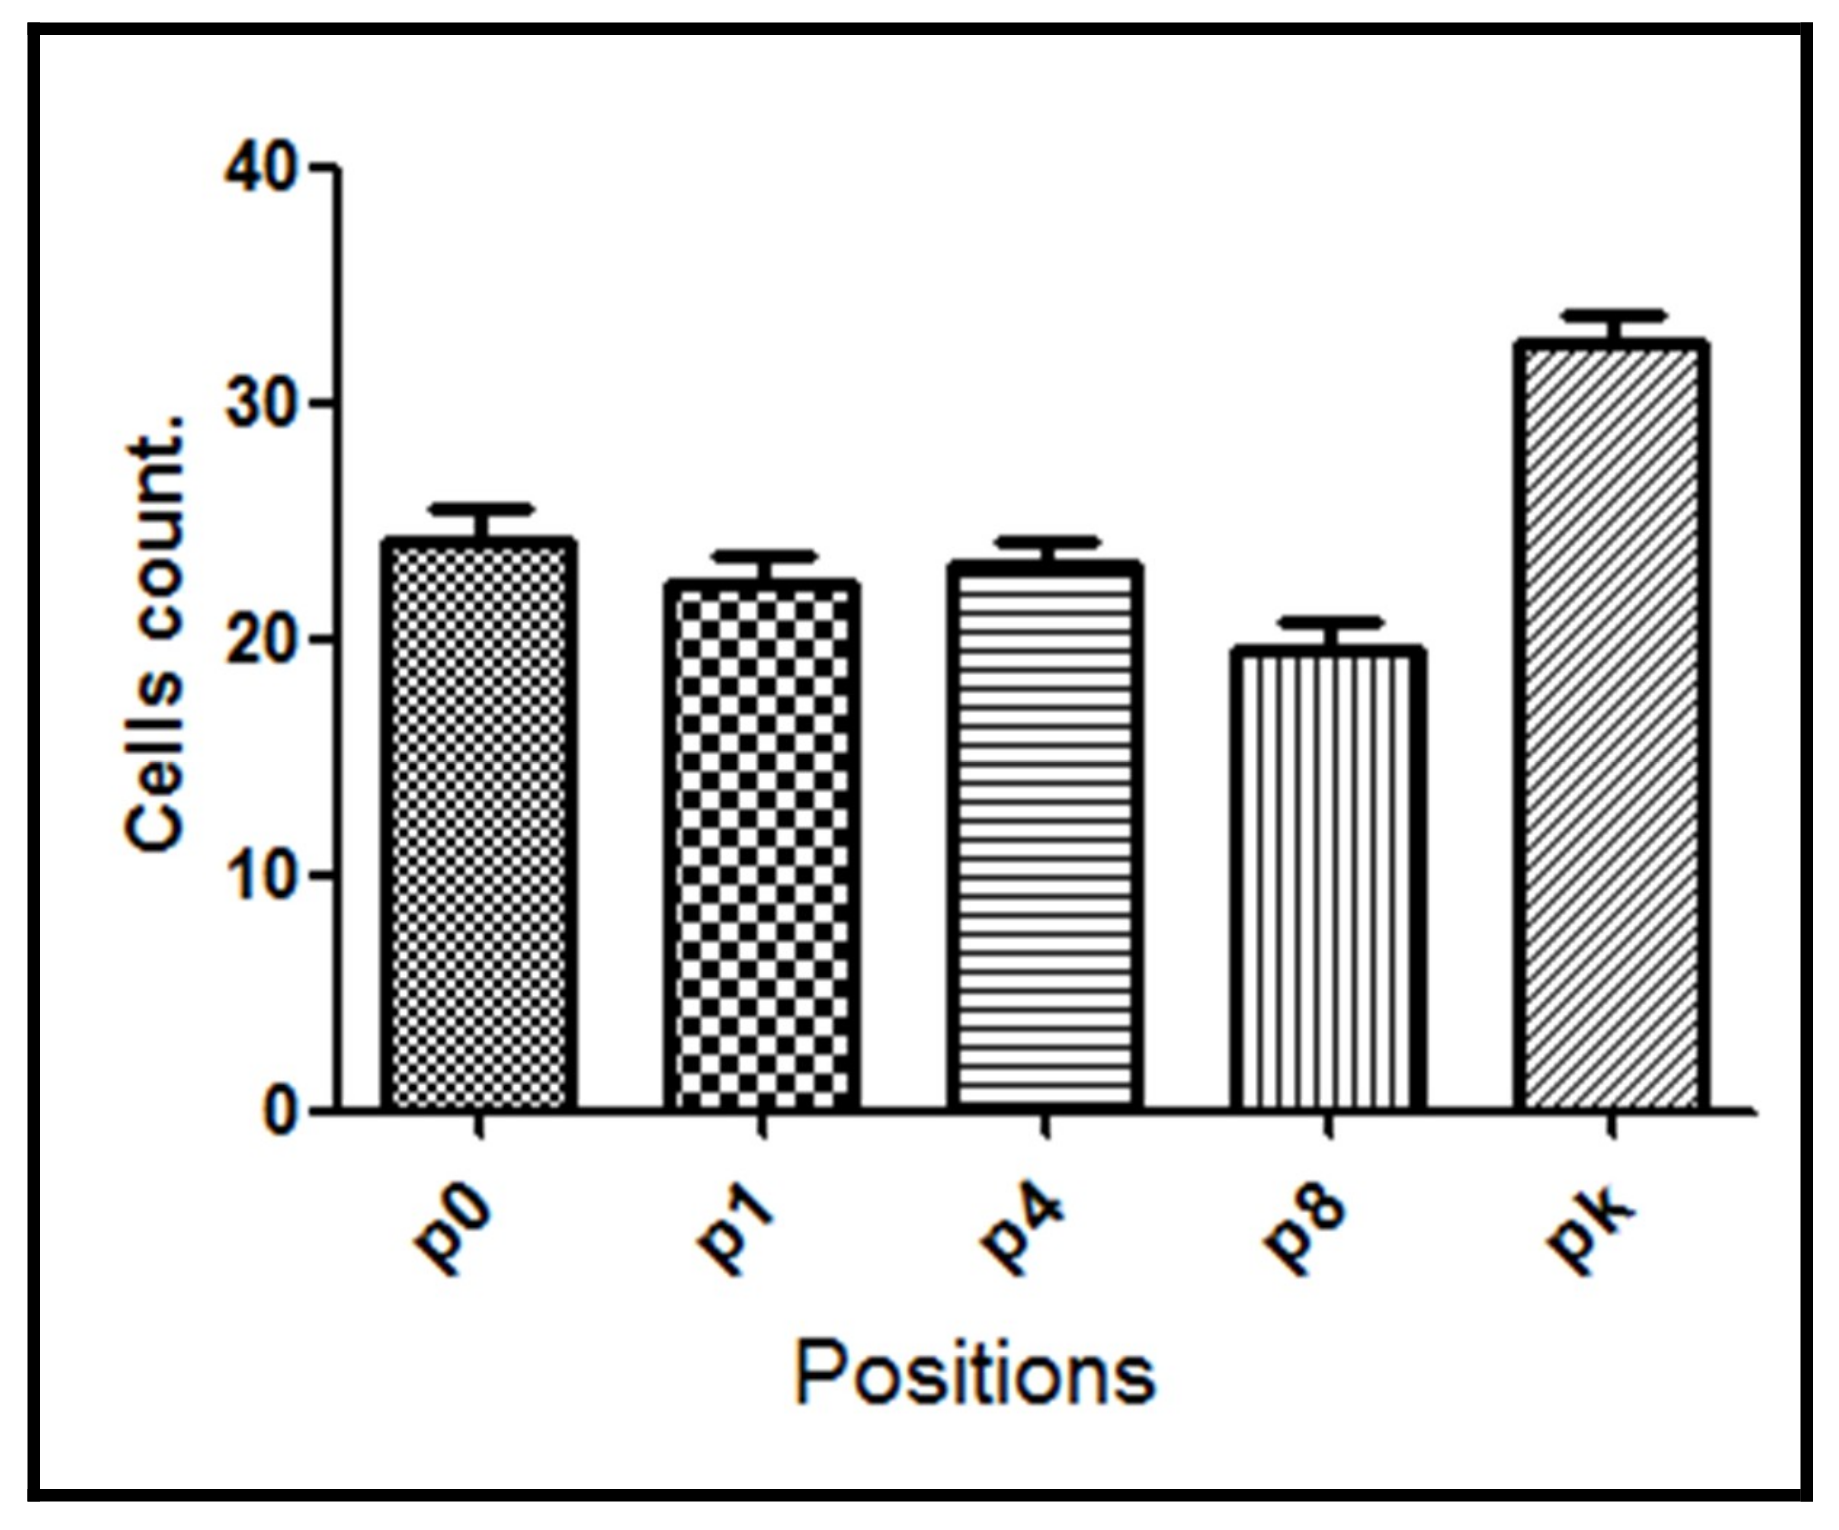

3. Results

| Group | p0 | p1 | p4 | p8 | pk | Average |

|---|---|---|---|---|---|---|

| G1 | 30.4 ± 2.24 | 35.4 ± 2.38 | 34.5 ± 2.56 | 35.8 ± 4.07 | 30.7 ± 0.98 | 33.4 ± 2.45 |

| G2 | 30.3 ± 2.03 | 27.4 ± 2.97 | 26.6 ± 3.00 | 24.0 ± 2.68 | 35.9 ± 2.85 | 28.9 ± 2.70 |

| G3 | 24.0 ± 3.47 | 22.4 ± 2.67 | 23.1 ± 2.29 | 19.5 ± 2.47 | 32.6 ± 2.70 | 24.3 ± 2.72 |

| G4 | 18.2 ± 2.36 | 21.2 ± 2.75 | 26.2 ± 2.48 | 33.2 ± 2.45 | 33.5 ± 2.94 | 26.5 ± 2.60 |